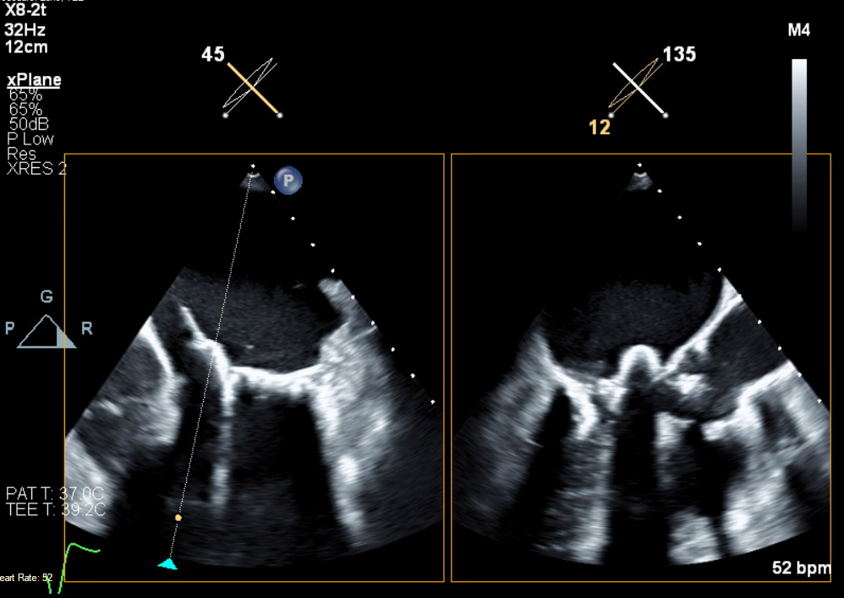

a snapshot from our recent #BASILICA case of a native aortic valve @UHZ_UNIFreiburg @dirkwestermann @HilgendorfIngo @PCRonline #TAVI #echofirst

Final echo showing no gradient across the LVOT and trivial PVL. Invasive hemodynamics also demonstrated no gradient.